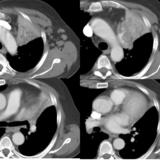

LUL Collapse Case 1 CT 4in1

Date: 02/19/2004

Views: 3518